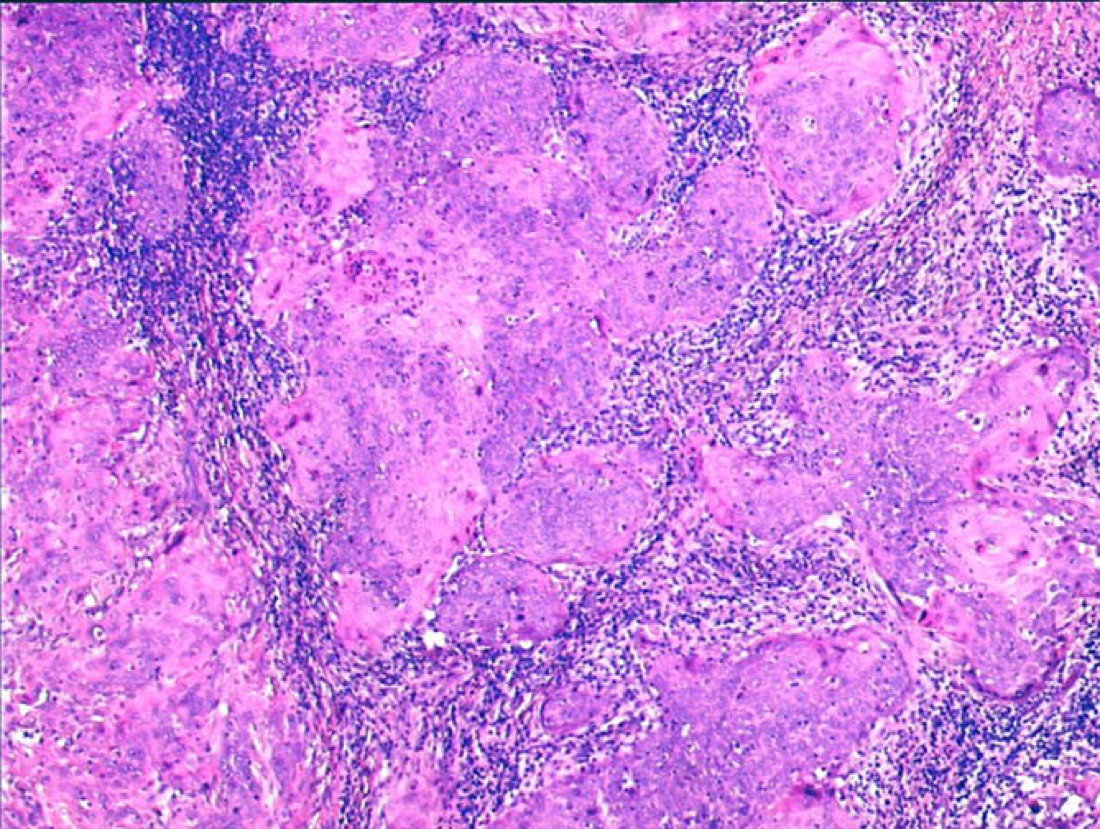

Endocervical curettage was performed and histology showed non-keratinizing squamous cell carcinoma.